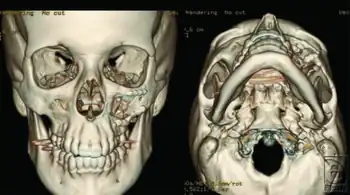

| Right zygomaticomaxillary complex fracture with disruption of the lateral orbital wall, orbital floor, zygomatic arch and maxillary sinus. | |

The zygomaticomaxillary complex fracture, also known as a quadripod fracture, quadramalar fracture, and formerly referred to as a tripod fracture or trimalar fracture, has four components, three of which are directly related to connections between the zygoma and the face, and the fourth being the orbital floor. Its specific locations are the lateral orbital wall (at its superior junction with the zygomaticofrontal suture or its inferior junction with the zygomaticosphenoid suture at the sphenoid greater wing, separation of the maxilla and zygoma at the anterior maxilla (near the zygomaticomaxillary suture), the zygomatic arch, and the orbital floor near the infraorbital canal.